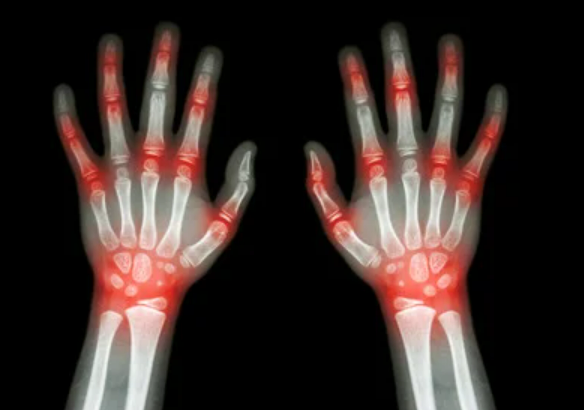

2. 통풍 증상 - 만성 관절염

통풍 증상을 그대로 참고 방치하게 되면 관절염을 더욱 가속화 시키게 됩니다. 이후 만성 관절염으로 악화될 수 있습니다.